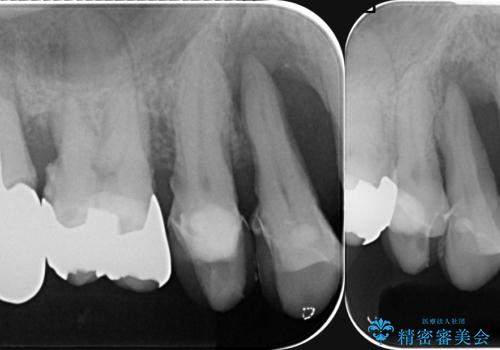

- 歯が全体的に揺れ始め、恐怖を感じ他院に相談に行ったところ、全体的な歯周病の問題・抜歯の必要性・入れ歯の提案を受け、入れ歯以外の選択肢を希望され来院されました。

全体的な歯周病検査を行い、多数の残すことのできない抜歯の必要な歯を認めたため、残せる歯に対しての徹底的な歯周病治療、失った歯に対しブリッジ・インプラント治療を全顎的に行っていくこととしました。